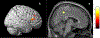

Results: The cancer group showed regional reductions over 12 months in frontal, temporal, and parietal gray matter on VBM, reduced FreeSurfer cortical thickness in prefrontal, parietal, and insular regions, and increased working memory-related fMRI activation in frontal, cingulate, and visual association cortex. Controls showed only reductions in fusiform gyrus on VBM and FreeSurfer temporal and parietal cortex thickness. Women with breast cancer showed higher estimated brain age and lower regional gray matter volume than controls at both time points. The cancer group showed a trend toward lower performance in attention, processing speed, and executive function at follow-up. There were no significant associations between brain imaging metrics and cognition or days on hormonal therapy.